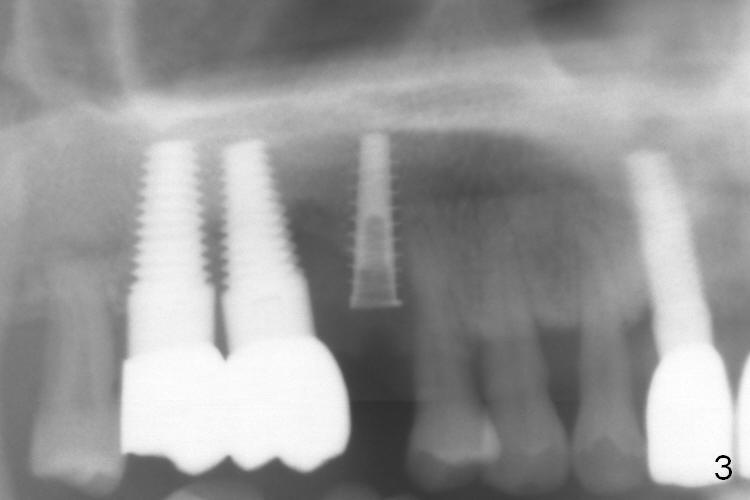

The distal buccal (Fig.1) and palatal (Fig.2) papillae (*) are recessive at the tooth #4.  Following extraction and use of 3.8 mm Magic Drill, a 4.5x13 mm implant is placed lower than the mesial crest (Fig.3) to reduce the chance of the distal implant thread exposure.  The latter is a measure to decrease peri-implantitis.  A 4.5x5.7(4) mm pair abutment is placed (Fig.4,5).  The remaining socket is filled with allograft/Osteogen placement.  The large space between #3 and 4 implants is occupied by the healthy gingiva, where bone graft cannot get in.